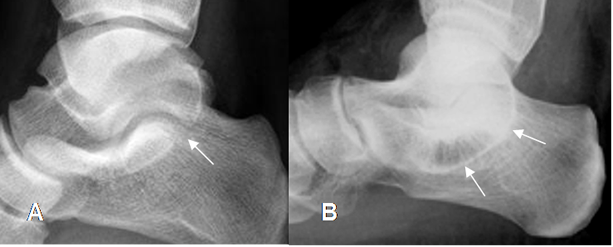

Fig 138. Coalición del tarso.

A y B: Rx lateral del tobillo. Signo de la “C” incompleto, como hallazgo normal en A. En B el signo de la “C” es completo, por coalición talocalcánea.